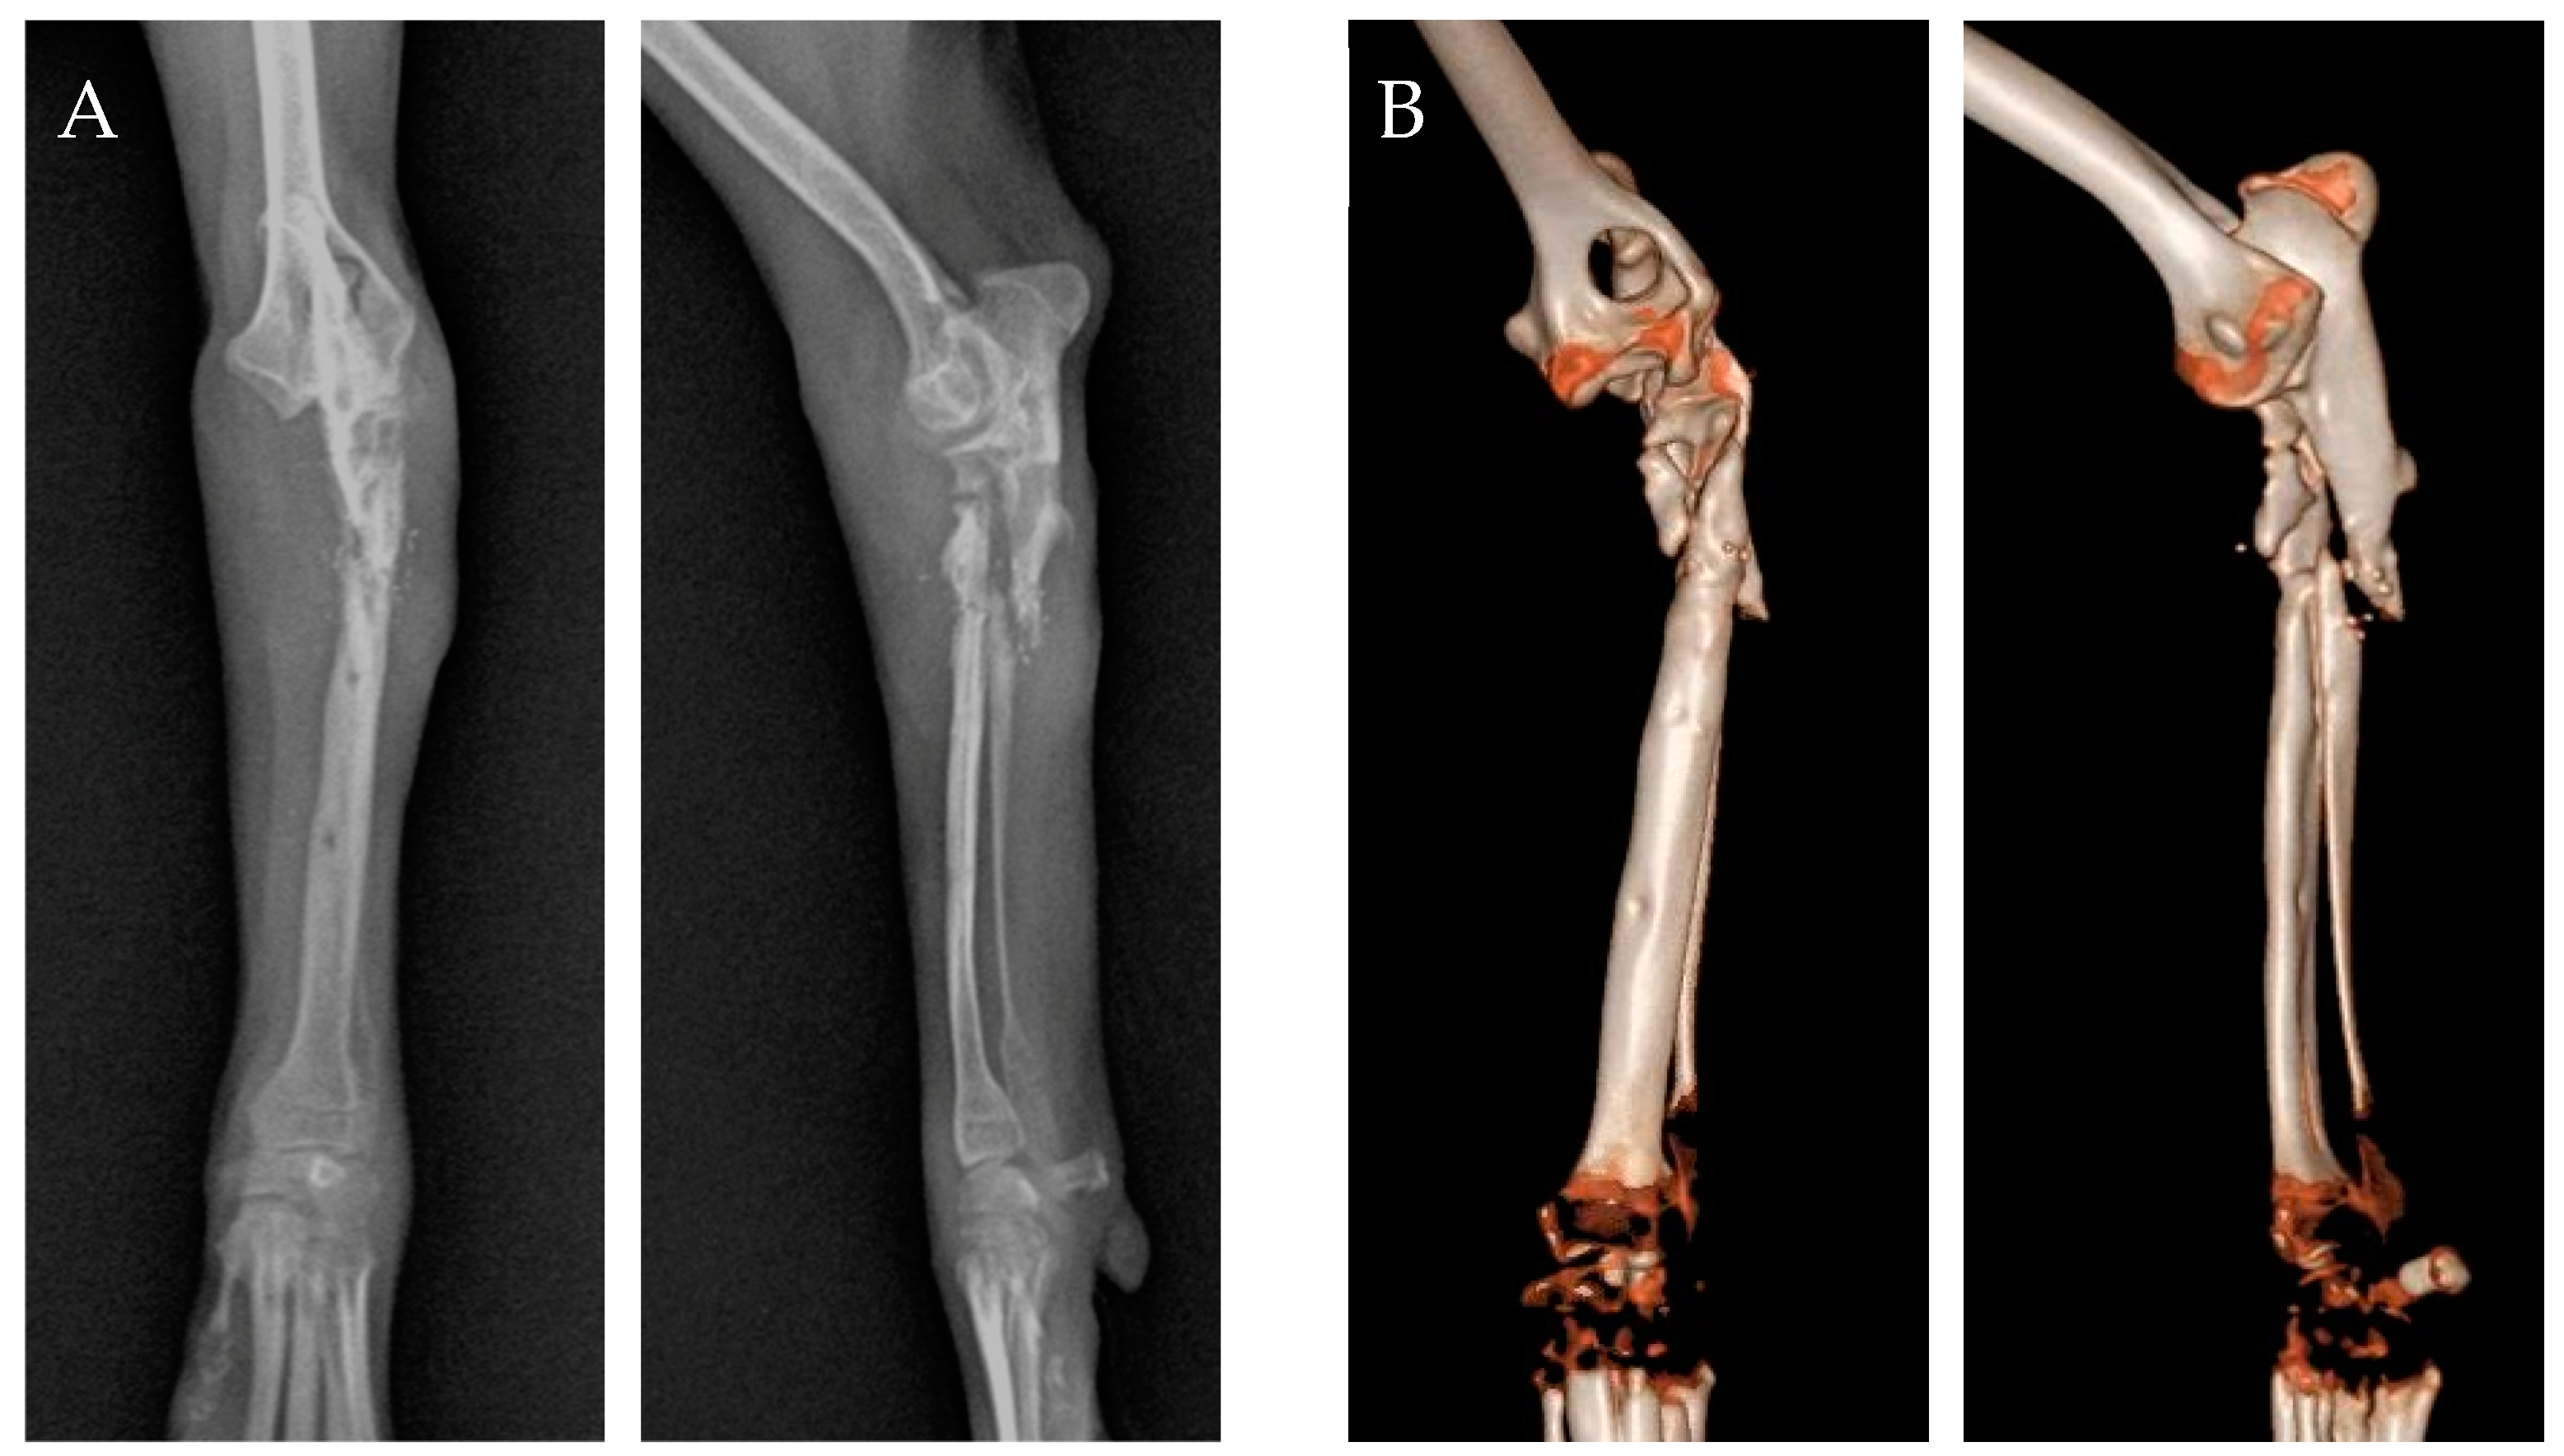

A 7-month-old, 3.3 kg, intact male Pomeranian suffered a complex fracture of the left proximal radius and ulna after falling. A tie-in IM pin was placed to fix the fracture at a private veterinary clinic; however, the fixation failed, and the fracture recurred. At referral, the patient could not weight-bear on the left forelimb during the standing physical examination. For subjective evaluation, the clinical lameness scores were used, which were based on six factors such as lameness score, range of motion (ROM), and pain, with each factor evaluated on a scale of 1 to 4 or 5 points (total score range: 6 to 27) [13]. Assessment using the clinical lameness score criteria revealed 24 points out of 27 points. Radiographs revealed poor bone healing due to the previous pin fixation and a comminuted fracture of the left proximal radius and ulna (Figure 1A). As the fracture was near the radial head, the bone structure was not clearly visible on radiography, necessitating a computed tomography (CT) scan for accurate fracture assessment and appropriate surgical planning. CT revealed a proximal non-reducible radial head fracture, which was fractured into three proximal fragments (6.5 mm × 5.9 mm, 7.5 mm × 2.9 mm, 10.4 mm × 4.1 mm), along with a proximal ulnar fracture (Figure 1B). Articular surface damage was also observed. Based on comprehensive examination, it was determined that stabilizing the radial head was essential to preserve the affected forelimb. Due to the radial head’s non-reducible fracture, direct stabilization through implant fixation was not feasible. Therefore, as a surgical treatment strategy, it was decided to apply a type II hybrid ESF, combining a bilateral uniplanar linear system with an Ilizarov-type circular system, to create space for the placement of two screws on the radial head.

Figure 1. (A) Preoperative radiography image. (B) Preoperative computed tomography reconstruction image.